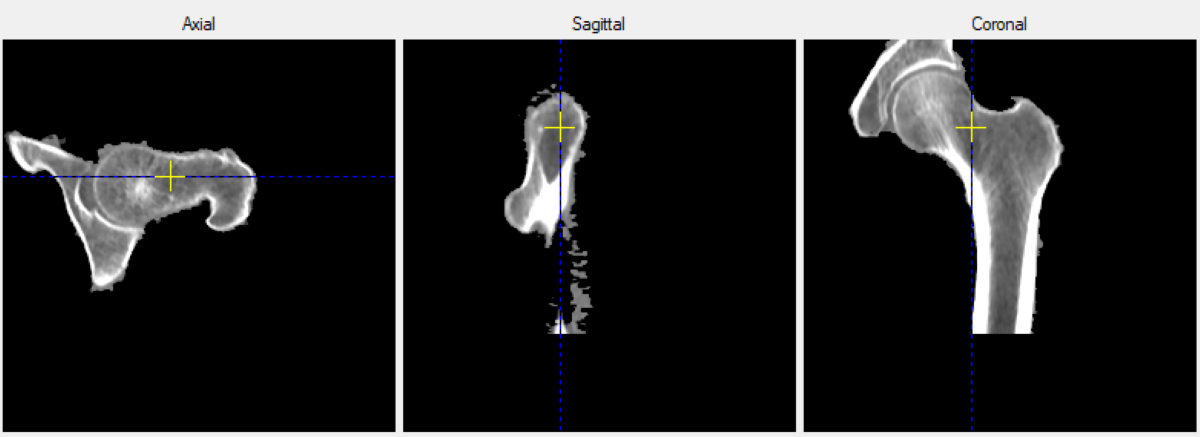

Сивакова и ее коллеги пришли к такому выводу при наблюдениях за состоянием здоровья ста пациентов с эпилепсией, получающих антиконвульсанты более 12 месяцев, и 58 здоровых добровольцев, никогда не принимавших таких лекарств. В ходе этих наблюдений исследователи отслеживали при помощи компьютерной томографии то, как прием этих препаратов влиял на минеральную плотность костной ткани, а также изучали то, как данные лекарства влияли на показатели минерального обмена.

КТ-исследование минеральной плотности бедренной кости. Источник: Наталия Сивакова

Результаты исследования минеральной плотности шейки бедра и всей бедренной кости. Источник: Наталия Сивакова